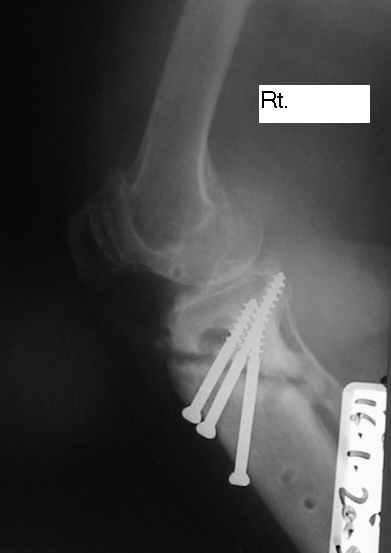

Dorogie Kollegy,Ko mne obratilas' bol'najia, ei 64 goda, ona stradaet ot dvuhstoronnego varusnogo gonoartroza, ei bila vipolnena Visokajia Ostotomjia goleny sprava 01.06.2004, zona osteotomii ne sroslas', plastina bila udalena 12.09.2004 (vidimo iz-za ee nestabilnosti), zona osteotomii tibia bila fixirovana 3-mjia shurupami. Seachas sylno bespokoyat boly v dvuh sustavah, hodit s trudom s pomoshyu Walker, a voobshe ona seachas na invalidnoi kolyaske. Podzkazite, pozhalusta, kak mozno ei pomoch' (snimky prilagayutsa)

U bol'nogo non-union osteotomii tibii. V vozraste 64 let, sdelal bi sleduiezhee:

Work out, proverit', net li infection: ESR, CRP, White cell Scan. Esli infection net togda est' dva varianta:

1. I predpochel bi ego: Total Knee Arthroplasty. Nuzhen budet Revision ( Long stem) tibial Component.

2. Ne sovetuiu delat' geroicheskix postumkov v otnoshenii Non union. Tut est' mnogo problem, ved' esteotomia provedena ne pravili'no s tochki zrenia deformazii. Orientazia ploskosto kollennogo sustava xotia ne ploxa v sagital'noii ploskosti, no vo frontl'noi idet sil;noie otklonenie narozhu i vniz. A nam tida ne nado.